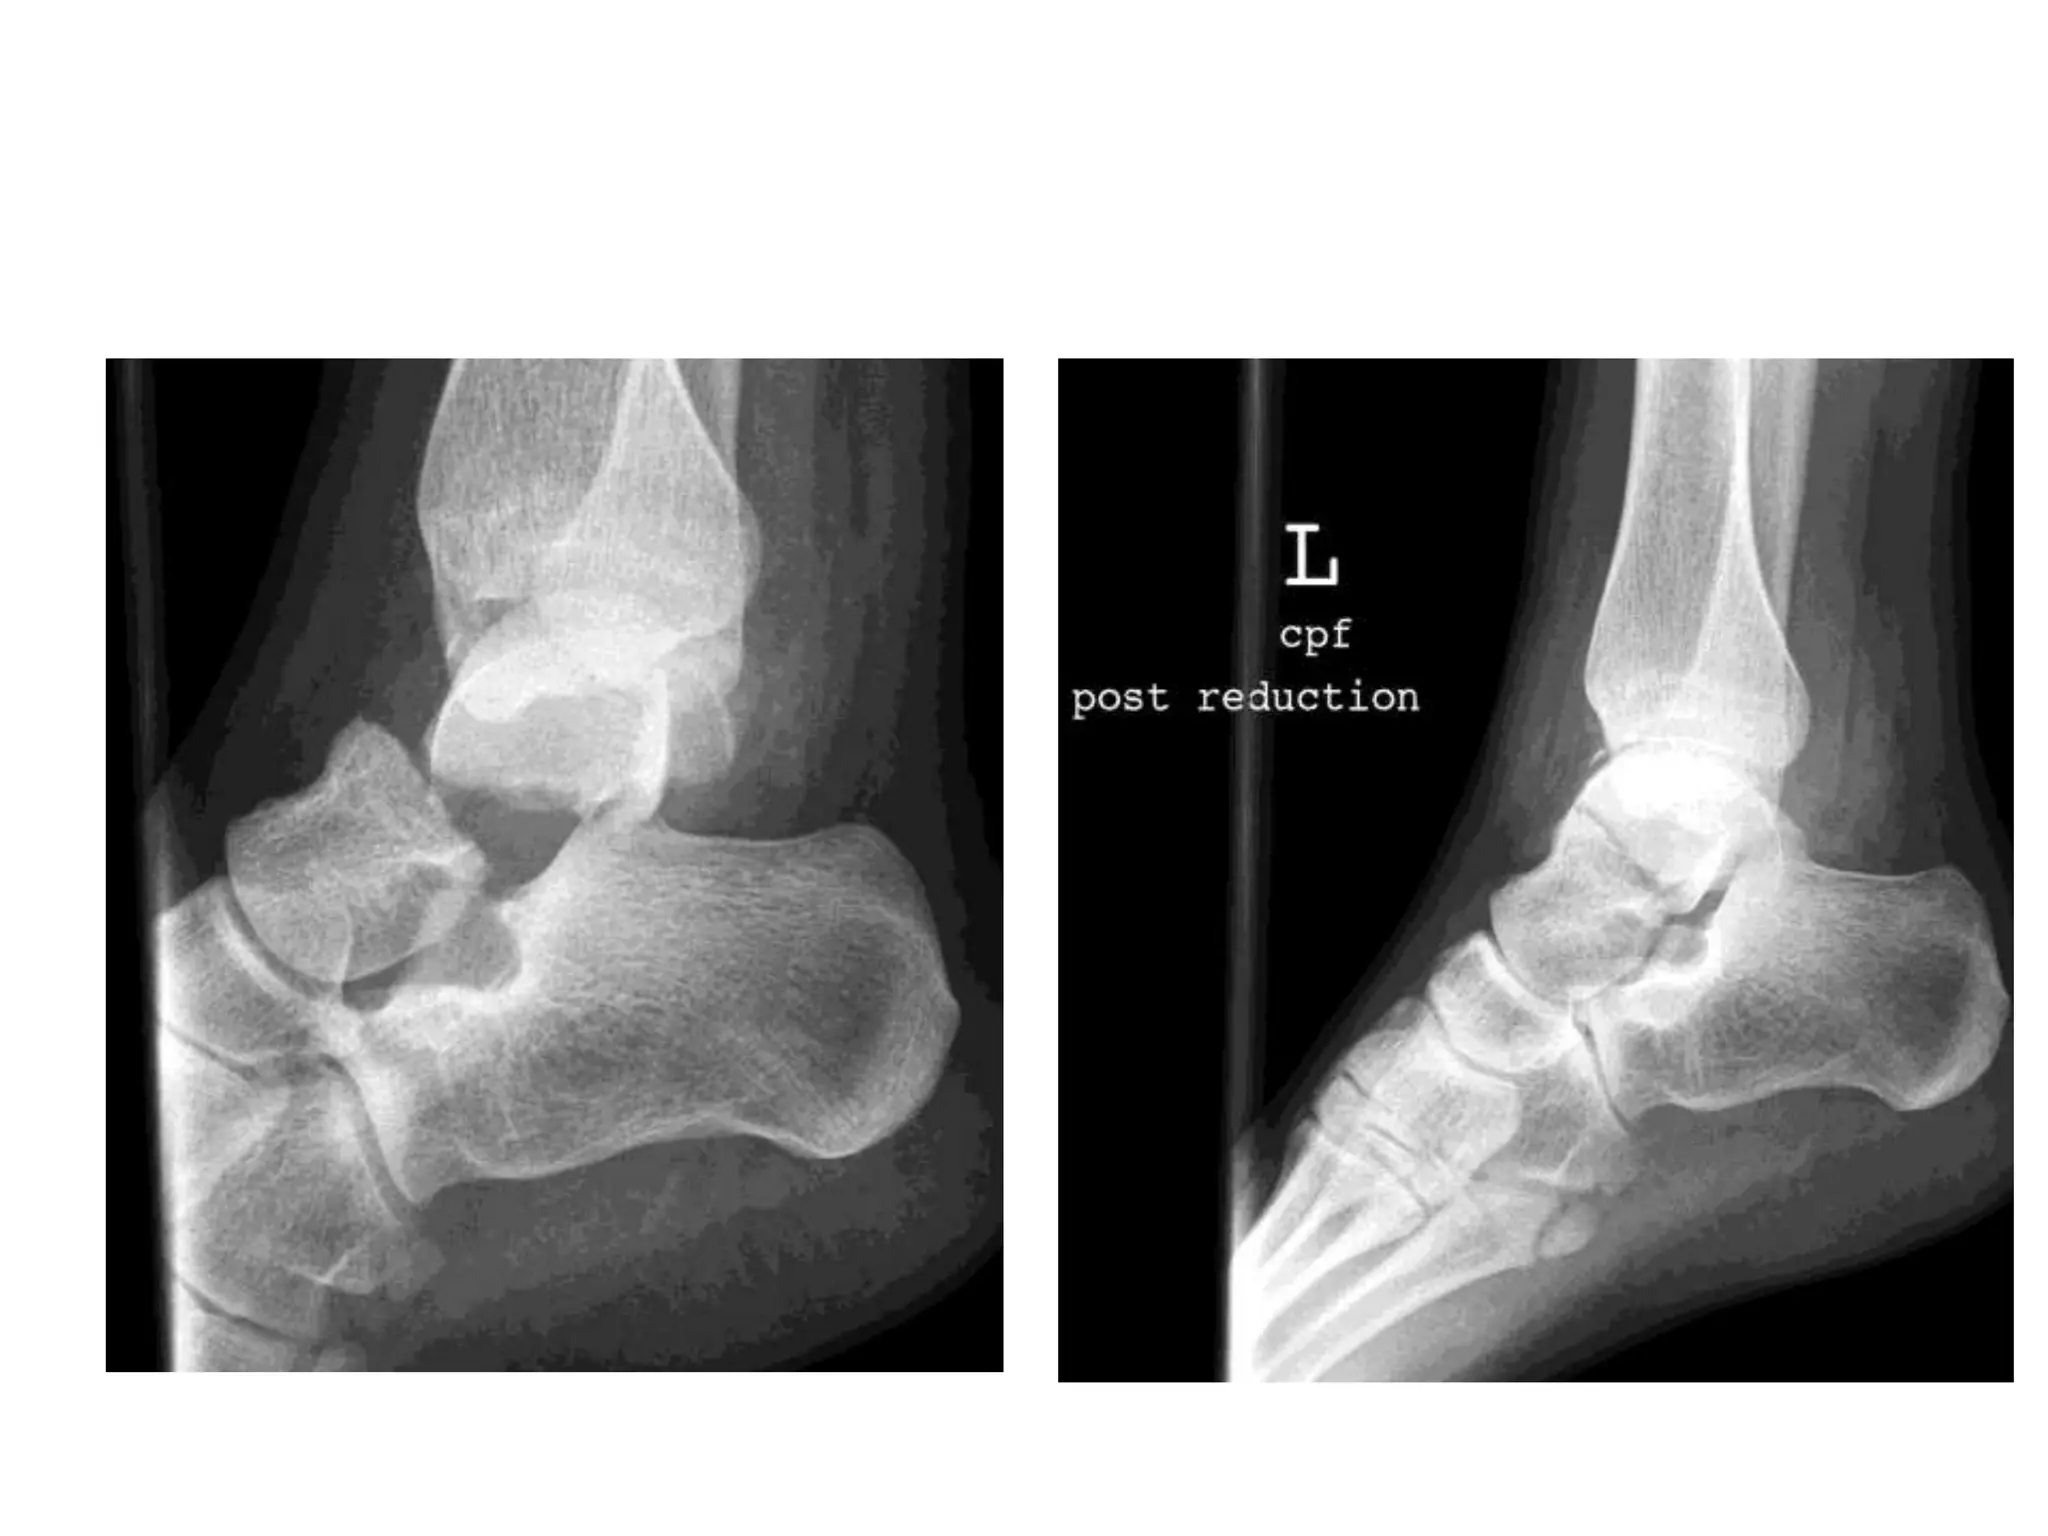

SUBTALAR DISLOCATIONS

• Spectrum of injuries

– Relatively Innocent

– Very Disabling

• Classification:

– Usually based upon

direction of dislocation:

– Medial dislocation: 85 %,

low energy

– Lateral dislocation: 15 %,

high energy

 Management of subtalar dislocation

• Urgent Closed reduction:

– Adequate sedation

– Knee flexion

– Longitudinal foot traction

– Accentuate, then reverse deformity

• Succesful in up to 90 % of patients